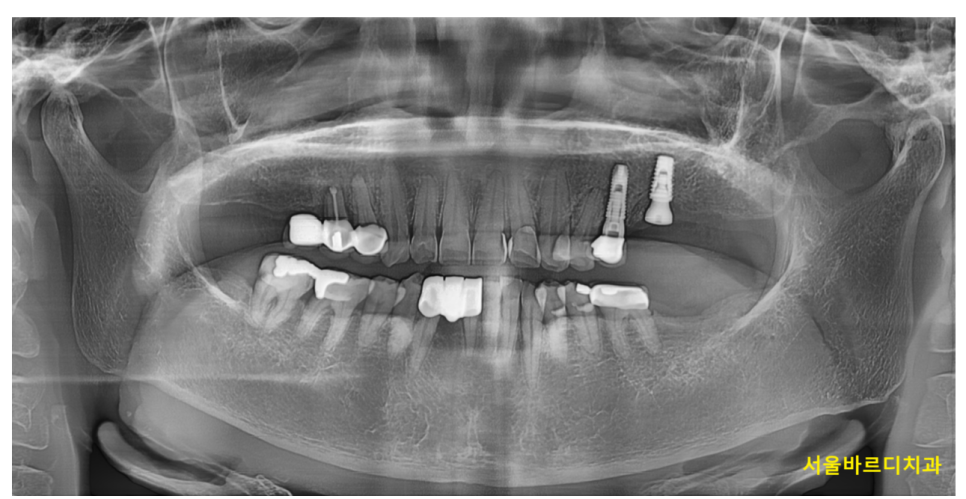

231023

250324